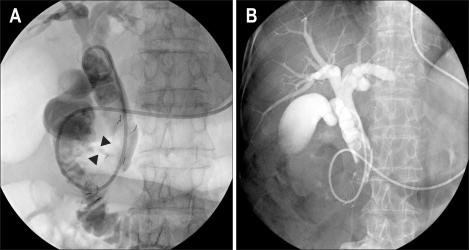

Fig. 3.

(A) Cholangiography reveals the linear track of the fistula from the mid-portion of the metallic stent to the duodenum, without contrast leakage (arrow head). (B) Follow-up cholangiography does not show the fistula tract.

Abdomen computed tomography (CT) showed an approximately 2 cm diameter cystic lesion between the duodenum and the mid-portion of the metallic stent, as well as upstream bile duct dilation (Fig. 1). The following day, the patient's abdominal pain spontaneously improved, and total bilirubin decreased from 15.2 mg/dL to 10.8 mg/dL. A subsequent endoscopy demonstrated that the bile had drained through a small fistula on the medial wall of the proximal second portion of the duodenum (Fig. 2A). The endoscopy also showed that the stent was impacted with food materials and stones (Fig. 2B). However, there was no stent migration or deformation on the end of the stent. When a mixture of indigo carmine and contrast was injected into the common bile duct, the contrast mixture was passed out the duodenum via the same fistula opening (Fig. 2C). As the dye was injected through an endoscopic nasobiliary drainage (ENBD) tube, fluoroscopy showed a linear track of the fistula from the mid-portion of the metallic stent to the duodenum, which was dissimilar to the CT finding. There was no evidence of contrast leakage into the extraduodenal abdominal cavity (Fig. 3A).

Seven days later, after placement of an ENBD tube and conservative management, including antibiotics, there was no fistula found from follow-up cholangiography (Fig. 3B). There was no evidence of tumor invasion on the fistula opening upon pathological examination.